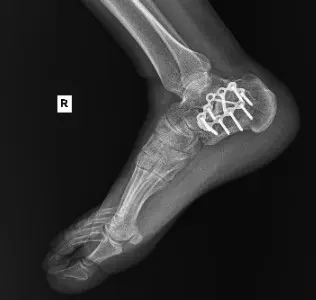

After continued symptoms, imaging revealed:

Post-traumatic subtalar osteoarthritis following calcaneus ORIF

The patient underwent right subtalar arthrodesis with hardware removal at a local medical center. Intraoperatively, significant post-traumatic changes, joint degeneration, and residual deformity were observed. A structural bone graft was placed, and internal fixation was used to achieve stability. The procedure was successfully completed with minimal blood loss.

Follow-up X-rays: Confirmed hardware in situ with robust fusion progression.